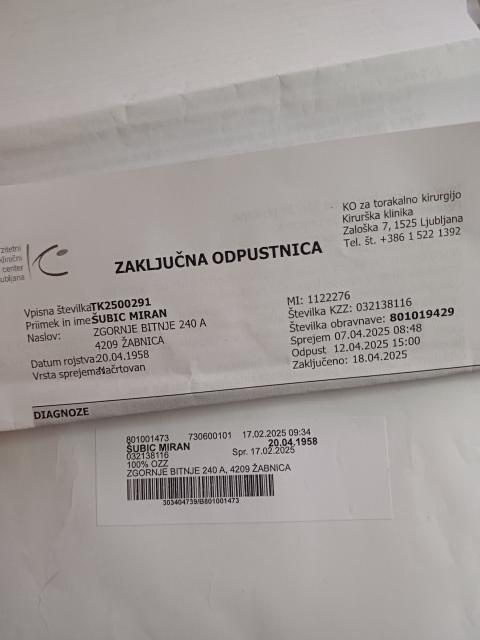

DIAGNOZA: RAK/10./ Skozi cilj prve etape, a nisem Pogi...

Čeprav sem zapustil intenzivno nego, še mislim na dni tam...

13. april 2025